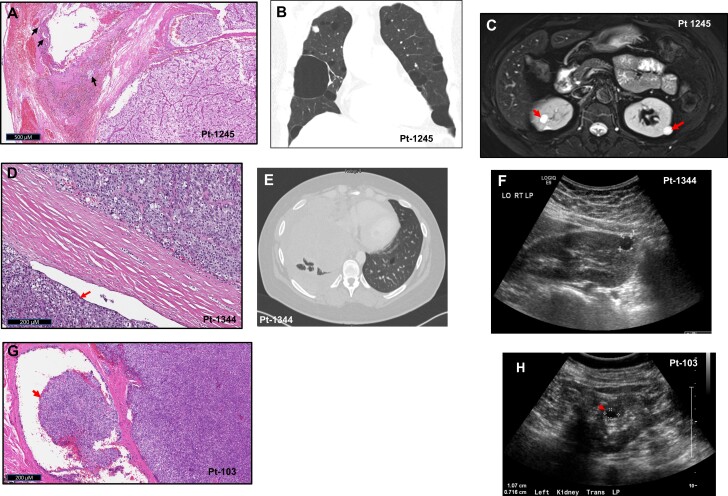

Figure 1.

Birt-Hogg-Dubé syndrome phenotype in patients with germline FLCN variants. A, Hematoxylin and eosin (H&E) staining of resected secondary parathyroid cancer from the most recent surgery for patient-1245 demonstrating vascular invasion (arrows). B, Chest computed tomography (CT) (coronal view) demonstrating multiple bilateral lung bullae in patient-1245. C, Abdominal magnetic resonance imaging scan of patient-1245 showing multiple predominantly cystic kidney nodules (arrows). D, H&E staining of resected primary parathyroid cancer from patient-1344 showing extension of tumor beyond the capsule (arrow). E, Chest CT (axial view) showing a large mass (pulmonary metastasis) compressing the right lung and pericardium and one of the multiple lung blebs on the left (arrowhead) in patient-1344. F, Kidney ultrasonogram showing unilateral 1.5-cm kidney cyst in patient-1344. G, H&E staining of resected parathyroid cancer recurrence from patient-103 showing extension of tumor through the capsule (arrow). H, Ultrasonogram of the left kidney showing unilateral 1.07-cm cyst in patient-103 (asterisk).

A 40-year-old Asian woman with primary hyperparathyroidism (initial ionized calcium 1.29 mmol/L, parathyroid hormone [PTH]: 178 pg/mL) underwent bilateral neck exploration with excision of a right-sided tumor that was histologically consistent with APT. She had persistent hyperparathyroidism but declined surgery until 5 years later, at which time a tumor histologically consistent with PC (Fig. 1A) was resected. She presented to our hospital at this time with persistent hyperparathyroidism and underwent 2 additional neck operations that were unsuccessful and was started on cinacalcet. Eighteen months later the patient reported dyspnea and dysphagia prompting a computed tomography (CT) scan, which revealed a right paratracheal mass compressing the trachea and bilateral lung blebs (Fig. 1B). She underwent right thoracotomy with resection of a 4.5 × 3 × 2.5-cm mediastinal mass with a prolonged postoperative course complicated by pneumothorax from a ruptured pulmonary bleb. Within 12 months, she had a recurrence necessitating reinitiation of cinacalcet along with denosumab, intravenous fluids, and sorafenib. Five years later, she developed compressive symptoms and underwent resection of an anterior neck mass histologically consistent with metastatic PC. Six months later, the patient continues to have hyperparathyroidism with redevelopment of a new anterior neck mass. She is a nonsmoker and has multiple bilateral cystic kidney tumors (Fig. 1C). No fibrofolliculomas are noted on examination.

A 34-year-old African American woman with incidentally diagnosed primary hyperparathyroidism underwent resection of the left inferior parathyroid, which was histologically consistent with PC (Fig. 1D), followed by subsequent surgical resection of the left thyroid lobe, central lymph nodes, and ipsilateral strap muscles and postoperative neck irradiation. Three years later, imaging studies revealed multiple liver and bilateral lung masses, the largest being a 3.4 × 1.6-cm lung mass with considerable mechanical lung compression. CT-guided biopsies of the largest lung and a liver mass were consistent with metastatic PC. She presented to our center at this time. Biochemical workup revealed a corrected serum calcium of 10 mg/dL (reference rage, 7.9-9.7 mg/dL), ionized calcium of 1.21 mmol/L (reference rage, 1.12-1.32 mmol/L), and PTH of 21.5 pg/mL (reference rage, 15-65 pg/mL). Six months later she presented with 30-pound (13.6 kg) weight loss, night sweats, and intermittent fevers. CT of the chest showed rapid growth of the lung tumors (largest measuring 11 cm), which were compressing the heart, liver, and major blood vessels. She died 2 years later at age 39. Her imaging revealed multiple small air-filled lung cysts (Fig. 1E) and a 1 to 1.5-cm right kidney cyst (Fig. 1F). No fibrofolliculomas or family history of kidney tumors were noted.

A 17-year-old White woman presented with primary hyperparathyroidism associated with a fragility fracture and kidney stones and underwent right inferior parathyroidectomy. She had a recurrence 3 years later and had a 3-gland parathyroidectomy that failed, requiring reoperation for resection of a right inferior parathyroid mass. Pathology on these surgeries were all benign. Two decades later, she presented to our center with recurrent hyperparathyroidism (corrected serum calcium: 12.4 mg/dL, ionized calcium: 1.7-1.8 mmol/L, PTH: 446 pg/mL). Imaging studies demonstrated a 2-cm mass in the right tracheoesophageal groove. A dense and hard mass adherent to the trachea and esophagus was resected with histology consistent with PC (Fig. 1G), with remission of hyperparathyroidism. Subsequently, the patient had another recurrence 4 years later with symptomatic hypercalcemia necessitating resection of a right level IV lymph nodes with histology consistent with PC. The patient is currently aged 66 years with an incidental finding of a 9-mm renal cyst (Fig. 1H). She does not have any lung cysts or fibrofolliculomas or family history of PC or BHD.

Subsequently, we identified 2 additional PC patients with germline FLCN variants. Patient-1344 was found to have the variant c.584delG (p.G195fs*28) (Fig. 2B), which has been previously reported in BHD patients (18, 19), while patient-103 was found to have a variant of uncertain significance (c.124G > C; p.G42R) (Fig. 2C). Patient-1344 was noted to have a 1.5-cm kidney cyst and multiple small lung blebs (Fig. 1D-1F), while patient-103 had no lung blebs but had a 1-cm kidney cyst in her solitary kidney (Fig. 1G and 1H). Sequencing of tumor tissue from 2 patients with no available germline DNA did not identify any pathogenic FLCN variants, suggesting absence of a germline FLCN variant in these patients.